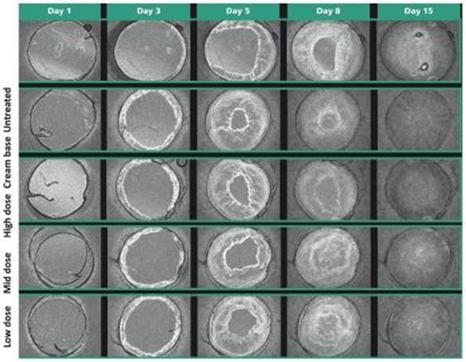

In addition to relief of symptoms, inflammation, pain, and others, we believe INM-755 may impact the underlying disease by enhancing skin integrity in a subset of EB patients. We have completed more than 30 preclinical pharmacology and toxicology studies to investigate the effects of CBN. Several of these nonclinical studies explored the effect on important symptoms such as pain and inflammation. In in vitro pharmacology studies, CBN demonstrated activity in reducing markers of inflammation. CBN upregulated expression of a type of keratin called keratin 15, or “K15”, which might lead to skin strengthening and reduced blister formation in EB simplex, or “EBS”, patients with mutations in another keratin called keratin 14, or “K14”. The anti-inflammatory activity of CBN may be beneficial in healing chronic wounds caused by prolonged inflammation. Following a review of our toxicology studies, the Netherlands National Competent Authority and Ethics Committee approved the initiation of a Phase I clinical study in healthy volunteers. We have safety data with INM-755 cream in 22 healthy adult volunteers from our first Phase I study (755-101-HV) in which subjects had the INM-755 cream applied to their upper backs daily for 14 days. An interim safety analysis of the first 16 subjects was reviewed by the Netherlands National Competent Authority and Ethics Committee and determined to be adequate to allow initiation of the second Phase I study testing INM-755 cream on small wounds. That second study has completed and we now have safety data for INM-755 cream applied to small open wounds daily for 14 days in 8 healthy adult volunteers.

A regulatory application to support our first Phase I clinical study in healthy volunteers with INM-755 (755-101-HV) was submitted November 4, 2019 and approved December 6, 2019. The initial Phase I clinical study evaluated the safety, tolerability, and pharmacokinetics of INM-755 cream in healthy volunteers with normal, intact skin; the volunteers had cream applied once daily for a period of 14 days. All subjects in this first clinical trial completed treatment and evaluations by March 27, 2020. A regulatory application was approved April 17, 2020, for a second Phase I clinical study of healthy volunteers to test the local safety and tolerability of applying sterile INM-755 cream to small wounds once daily for 14 days. As with the initial Phase I trial, the second trial (755-102-HV) was conducted with two different drug concentrations and a vehicle control. Enrollment began in early July 2020 and the clinical trial completed treatment and evaluations at the end of September 2020. The safety of INM-755 will continue to be assessed throughout its clinical development.

In preclinical pharmacology studies, CBN demonstrated activity as an anti-inflammatory and antinociceptive agent. CBN upregulated expression of keratin 15 (K15), which might lead to skin strengthening and reduced blister formation in EBS patients with keratin 14 (K14) mutations. At the cream concentrations chosen for clinical development, it does not appear to impede wound healing of partial-thickness wounds. Its anti-inflammatory activity may be beneficial in healing chronic wounds caused by prolonged inflammation.

We have completed 20 safety pharmacology and toxicology studies to investigate the effects of CBN. We have also completed three Phase 1 safety and tolerability studies in healthy volunteers, two studies of which were conducted with varying concentrations of INM-755 cream and one study of which examined the non-CBN components of the cream base for INM-755.